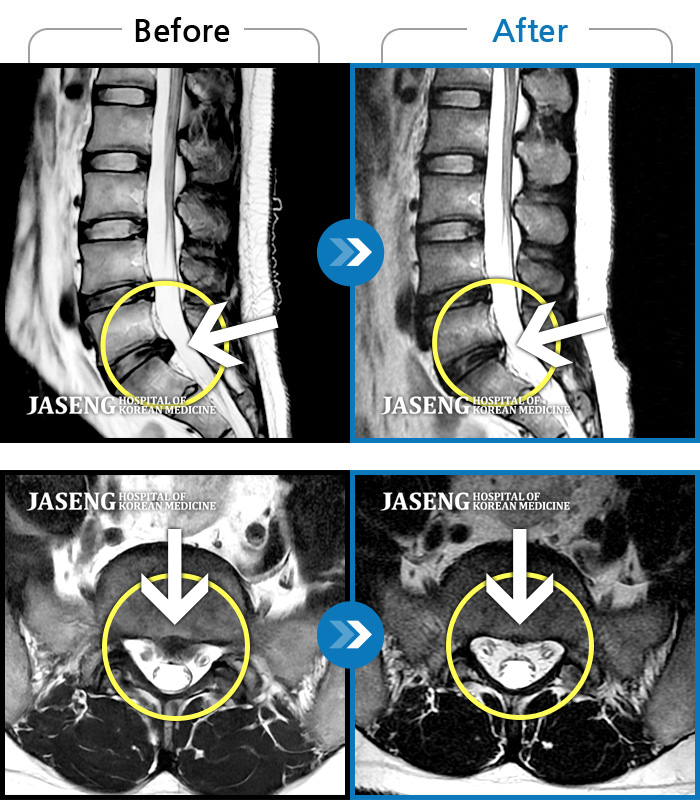

지난 4월말 허리 통증으로 고생을 하다가 척추 전문 병원을 찾았었습니다.

MRI 촬영 결과 디스크에 척추관 협착이라는 병명으로 무작정 수술을 권유 받았습니다.

내 영상자료를 보고 상세한 설명에 신뢰를 느낄 수 있었고,

추나약물요법및 추나 요법 ,약침, 봉침을 통한 치료 받기를 3개월~~

길다면 길겠지만 꾸준한 치료 덕분에 비수술치료법을 통해

새로운 생활을 하고 있습니다.

추나약물요법을 통한 염증제거 및 인대 강화로 인해 많은 효과를

본걸로 생각이 듭니다.